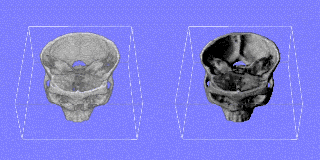

Figure 2:

3D fusion of MR image and simulation of the heat distribution during LITT

Figure 3:

Simulated damage volume (blue) in comparison with the actual laser lesion (confined by the white gadolinium rim) induced in this patient